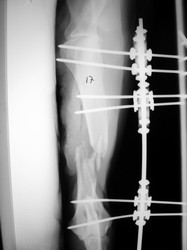

Fijación Externa

Fijación externa en IVOT

PRÁCTICAS CURSO DE FIJACIÓN EXTERNA PERFECCIONAMIENTO.

Húmero.